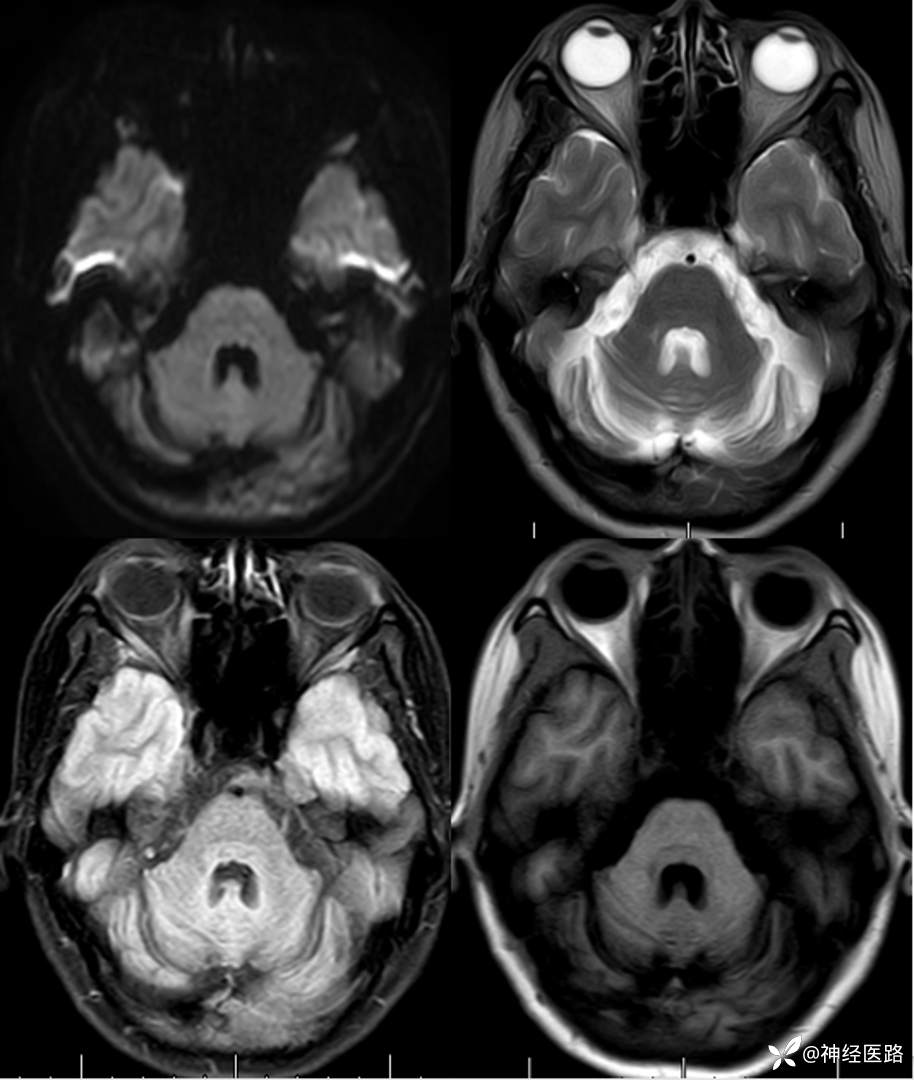

辅助检查:头部磁共振: 1.左侧额叶及右侧顶叶白质内高信号,请结合临床及相关检查。2.双侧小脑半球脑萎缩。3.部分颅骨信号增高。